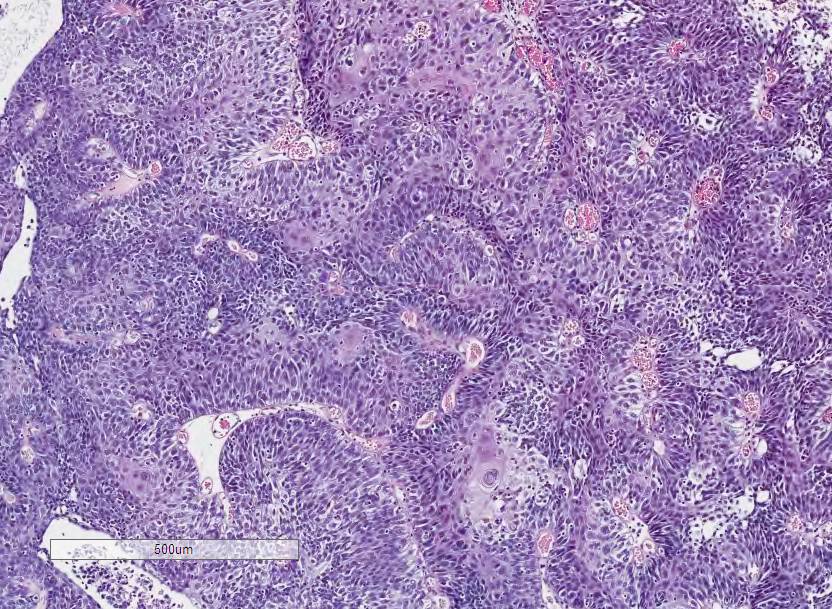

Bladder Papillary Lesions

Case ID: 640

Papilloma

PUNLMP

Low-grade papillary urothelial carcinoma (LG-PUC)

High-grade papillary urothelial carcinoma (HG-PUC)